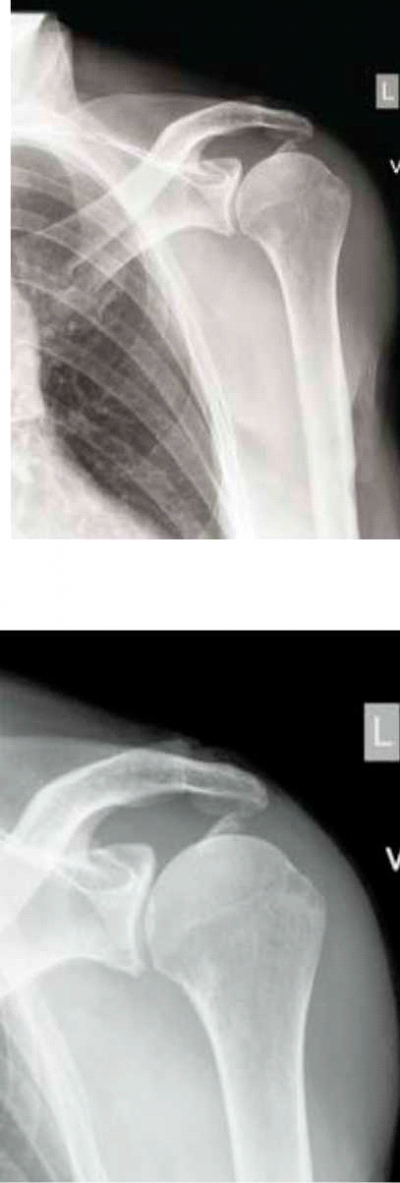

שברים בעצמות הכתף

שברים בכתף מתרחשים עקב חבלה ישירה או עקב חבלה עקיפה בעקבות נפילה. את שברי ראש עצם הזרוע נהוג לחלק לפי מספר חלקי השבר (שני חלקים, שלושה וארבעה). ככל שמספר החלקים ומידת תזוזתם עולים, עולה גם מורכבות השבר. ניתן לטפל בשברים בכמה שיטות. במידה ותזוזת חלקי השבר מזערית השיטה המועדפת היא הגישה השמרנית, הלא ניתוחית, הנותנת דגש על טיפול תמיכתי בכאב ופיזיותרפיה. בגישה הניתוחית, ניתן לקבע את השבר בניתוח מינימלי, ללא פתיחה של השבר, על די החדרת מסמרים ארוכים או ברגים דרך העור, בדרך כלל עם תוספת של קיבוע חיצוני לייצוב השבר. במקרים אחרים יש צורך לחשוף את השבר בניתוח ולחבר חזרה את כל חלקי השבר בעזרת ברגים, ולעיתים גם פלטת מתכת.

במקרים שהסיכוי להחלמת השבר בצורה שתאפשר תפקוד הוא נמוך, יש לשקול החלפה של העצם בתותב ממתכת. במקרים יחודיים של שברים עם תלישת גידים ניתן לתקנם ארטרוסקופית תוך איבחון וטיפול בפגיעות נוספות כגון קרעי גידים ורצועות.

| תמונה 2. חיבור שבר בכתף, תמונה עליונה לפני, תמונה תחתונה אחרי |

בקרב מבוגרים שברי הכתף הם בעיקר של ראש עצם הזרוע ונגרמים עקב אוסטאופורוזיס. בגיל הצעיר השברים האופיינים הם של עצם הבריח (Clavicle) והסובב אותה לרוב כתוצאה מחבלות משמעותיות או כתוצאה מפריקת כתף. השברים יכולים להיגרם בצורה ישירה או עקיפה, כגון נפילה על המרפק או על שורש כף היד.

בשברי עצם הבריח הטיפול השמרני מוצלח לרוב ורוב החולים ייהנו מחזרה לתפקוד מלא. שברים עם תזוזה משמעותית עלולים להוביל לאי חיבור בכ-30 אחוזים מהמקרים ולתפקוד לקוי של הכתף. במקרים אלו נדרש טיפול ניתוחי שכולל שחזור חלקי השבר וקיבועו, לרוב בעזרת פלטה וברגים.